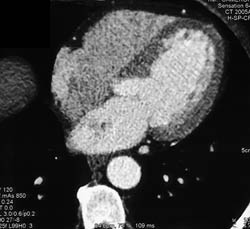

Repaired Aortic Root With Implanted Coronary Arteries